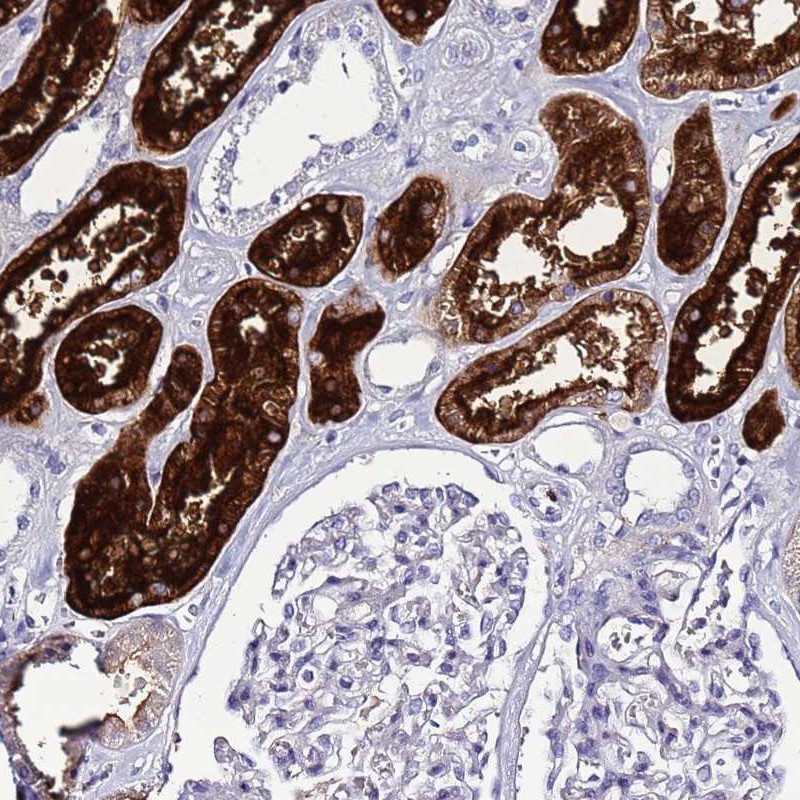

Immunohistochemical staining of human kidney shows strong cytoplasmic positivity in renal tubules.